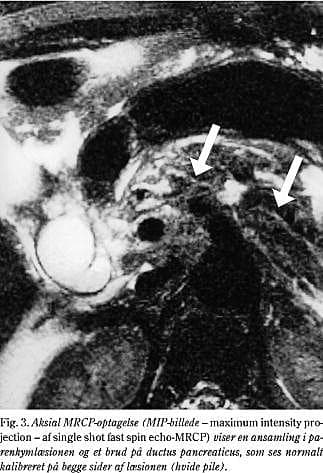

2. En 55-årig mand blev indlagt ca. 12 timer efter at være blevet sparket i abdomen. Patienten klagede ved indlæggelsen over tiltagende øvre abdominalsmerter. Objektivt fandtes han upåvirket og afebril. Blodtrykket blev målt til 150/60 mmHg og pulsen til 80. Abdomen fandtes blødt og med lokaliseret ømhed i epigastriet og ud under begge kurvaturer, men uden diffus peritonealia. S-amylase var på 542 U/l og leukocyttallet på 14,6 mia/l. Dynamisk CT (Fig. 2) viste et moderat ødem samt et tværgående hæmatom i corpus pancreatis. Den følgende dag var S-amylase steget til 2.228 U/l. En MR-scanning viste, at der var en læsion i corpus pancreatis, og ved MRCP (Fig. 3) blev der påvist diskontinuitet af ductus pancreaticus major. Ved laparotomi fandt man et hæmatom omkring milten samt en ruptur i pancreas ved collum pancreatis med overrevet ductus pancreaticus major. Der blev foretaget resektion af cauda og corpus pancreatis samt splenektomi. Det postoperative forløb var kompliceret af sekretion fra pancreasresektionsranden. Dette blev drænbehandlet med ophør af sekretion efter tre uger.

MR-scanning, og specielt MRCP, har større bløddelskontrast end CT, og er sandsynligvis diagnostisk mere valid end CT til påvisning af parenkymlæsioner og afklaring af integriteten af ductus pancreaticus. Der foreligger fortsat ingen større randomiserede studier heraf, men Fulcher et al (15) anfører på baggrund af et mindre materiale med overvejende stumpe traumatiske pancreaslæsioner, at MRCP præcist og hurtigt kan vise ductus pancreaticus. Denne opfattelse støttes af flere kasuistiske meddelelser (16, 17). MRCP blev kun foretaget i sygehistorie 2, hvor der blev påvist diskontinuitet af ductus pancreaticus.